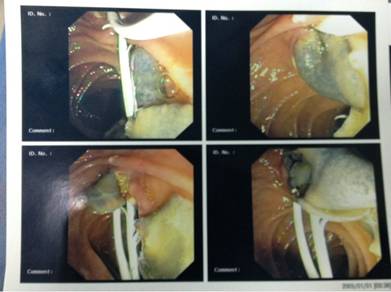

-Về mặt giải phẩu bệnh, đường mật luôn luôn dãn rộng, đường kính lớn hơn 1,5-3 lần so với bình thường, hay gặp nhất trong các trường hợp tắc đường mật (Khorcandi và cs., 1977), nang nhỏ trong ống mật có thể quan sát thấy đầu tụy to ra và chắc (Maroy và cs.,1987). Nếu tắc mật thì túi mật thường to ra, phù nề, kích thước có thể đến 7 x 12 x 7cm, bờ dưới có thể sa đến ngang rốn (Chen và Mott., 1990). Xơ hóa túi mật với các tổ chức lân cận rất thường thấy, sỏi ống mật hay túi mật cũng hay gặp, thường là sỏi nhỏ và số lượng sỏi nhiều (Wong và cs., 1985; Chen và Mott., 1990; Arjona và cs., 1995). Thành phần bên trong đường mật và túi mật có thể chứa hỗn hợp máu, dịch mật, cặn máu đông và cặn sơi tơ huyết fibrin, chất mụn nát, đôi khi có cả mủ và máu trộn lẫn (Huỳnh Hồng Quang và Lê Quang Quốc Ánh., 2005);